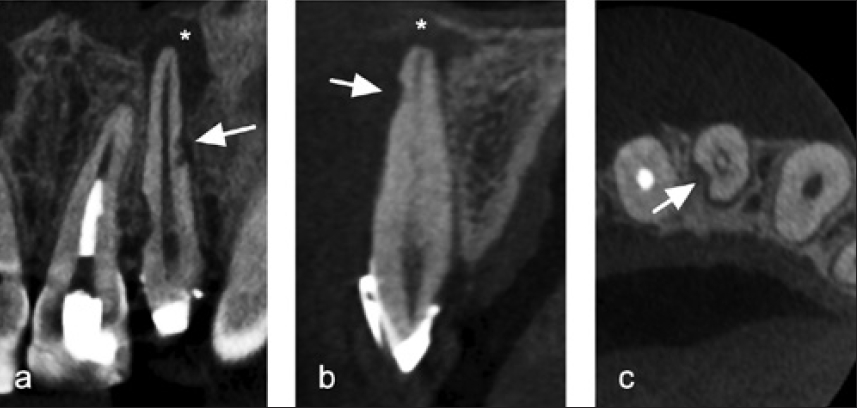

Da invasive zervikale Resorptionen von der Eintrittspforte ausgehend komplexe Ausbreitungsrichtungen wählen, ist es im Rahmen der Diagnostik essenziell, das Ausmaß und die Lokalisation exakt zu bestimmen, um die therapeutischen Möglichkeiten optimal einschätzen zu können. Hierzu diente klassischerweise die Einteilung nach Heithersay (Abb.10a) [29].

Dr. Widbiller

Klasse 1 beschreibt dabei eine kleine zervikale Läsion im oberflächlichen Dentin, wohingegen eine Resorption der Klasse 2 in pulpanahes Dentin vordringt. Die Klasse 3 liegt bei Ausbreitung bis in das zervikale Drittel der Zahnwurzel vor und von Klasse 4 spricht man, wenn sich der Defekt bis mindestens in das mittlere Wurzeldrittel erstreckt [29]. Da die dreidimensionale Ausbreitung des Resorptionsgewebes dabei unberücksichtigt bleibt, definierten Patel et al. ein dreidimensionales Bewertungssystem auf Basis der digitalen Volumentomografie (DVT) [30]. Demzufolge wird, wie in Tabelle 1 dargestellt, neben der Höhe (1 bis 4) und der Kanalnähe (d und p) auch die periphere Ausdehnung des Defektes (A bis D) in die Beurteilung einbezogen (Abb. 10b und c).